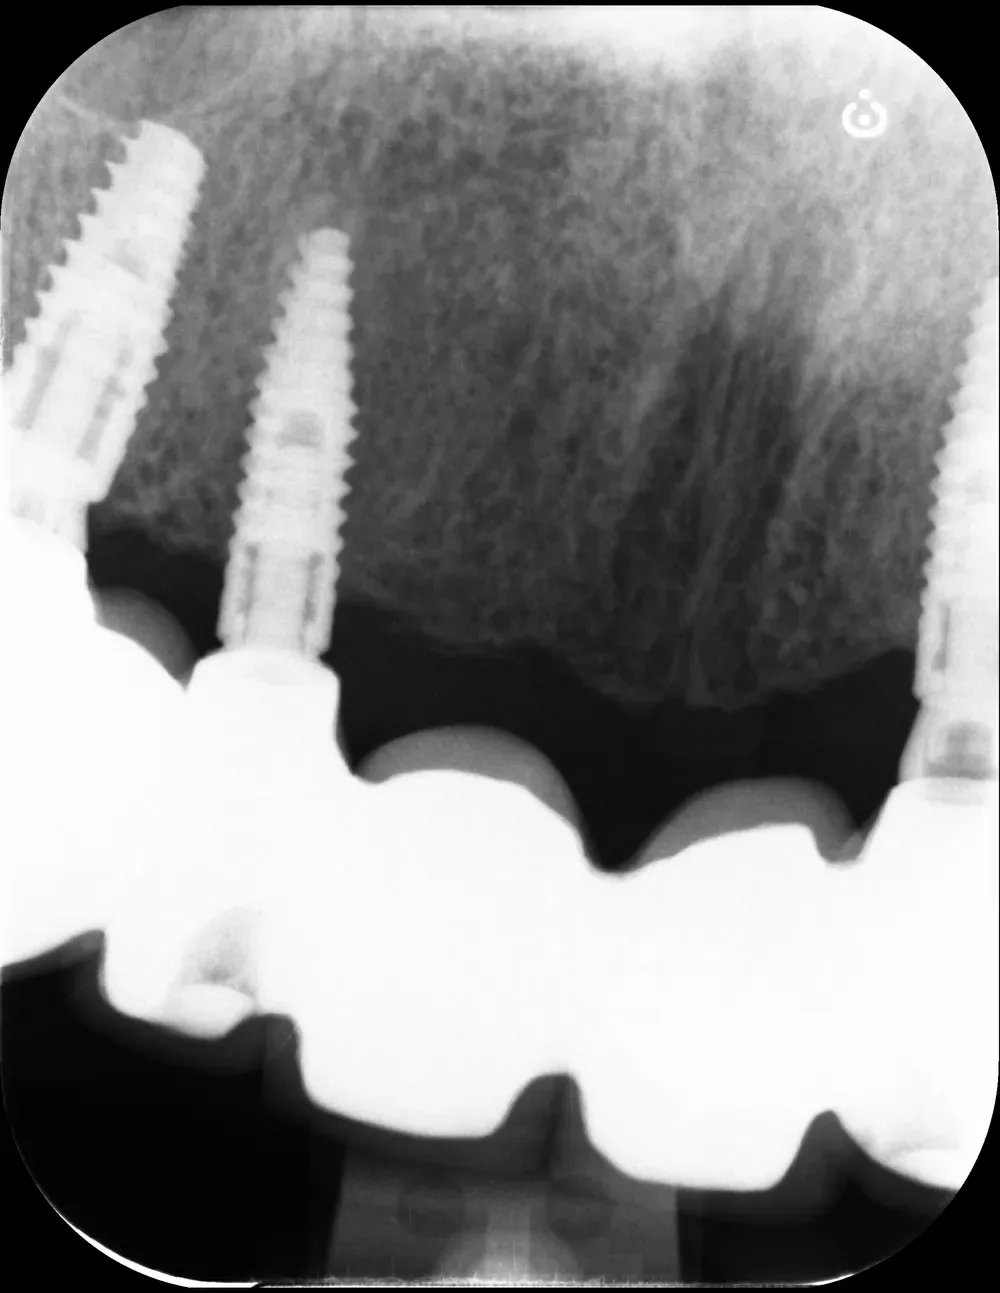

Il mascellare superiore destro era affetto da atrofia categoria S3 CCARD in posizione 16 e S2 CCARD in posizione 14 (precedentemente estratto), con presenza di cisti da ritenzione mucosa e setto di Underwood.

Inserimento impianti con rialzo del seno e aspirazione cisti da ritenzione mucosa del seno mascellare

Ho inserito due impianti, in posizione appunto 16 e 14, con minirialzo del seno mascellare e aspirazione della cisti da ritenzione mucosa tramite accesso laterale.